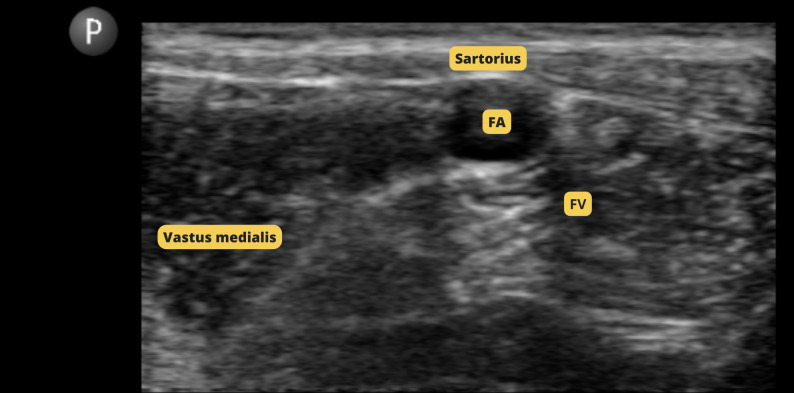

Orthopedic procedures are associated with severe postoperative pain. In TPLO, the block commonly used is the sciatic nerve block associated with the femoral nerve block. In orthopedic surgeries in human medicine, the iPACK block associated with the adductor canal block has been used as alternatives that do not affect the strength of the quadriceps femoris muscle. The objective of this study was to evaluate the trans and postoperative analgesic effect of the association of iPACK block and adductor canal block, as well as to evaluate the patient's motor recovery after surgery. Four patients were selected, without distinction of breed and gender, weighing more than 22lb, referred to TPLO. All patients underwent the combination of iPACK block and adductor canal block with 0.5% bupivacaine. The intraoperative evaluation was carried out by measuring mean arterial pressure, heart rate and respiratory rate, and all patients were stable during the procedure. The postoperative evaluation was carried out based on the assessment of pain using the modified Glasgow scale, in which all patients scored less than 05/24, and assessment of ambulation through videos using the adapted Muzzi scale, presenting ambulation between grade 1 and 2. No patient required intraoperative or postoperative analgesic rescue.